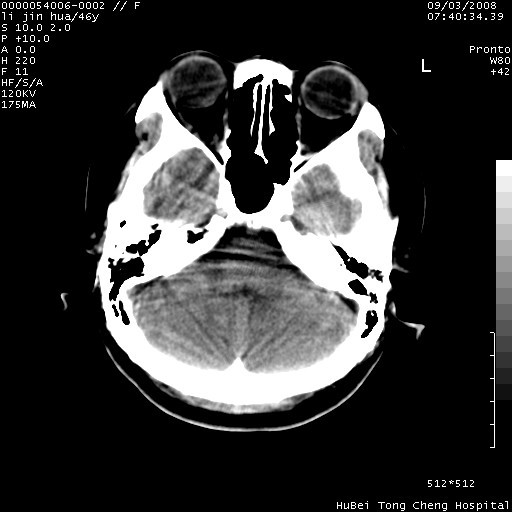

以下是引用panyishengct在2008-9-6 1:47:00的发言:[br]病史?[br]左侧枕/顶叶见一等/低混杂密度占位,壁完整,厚薄较均匀,其前方似有一类似小病灶,周围有水肿带,请结合病史考虑,脓肿可能,不排外转移瘤或胶质瘤,建议增强扫描。